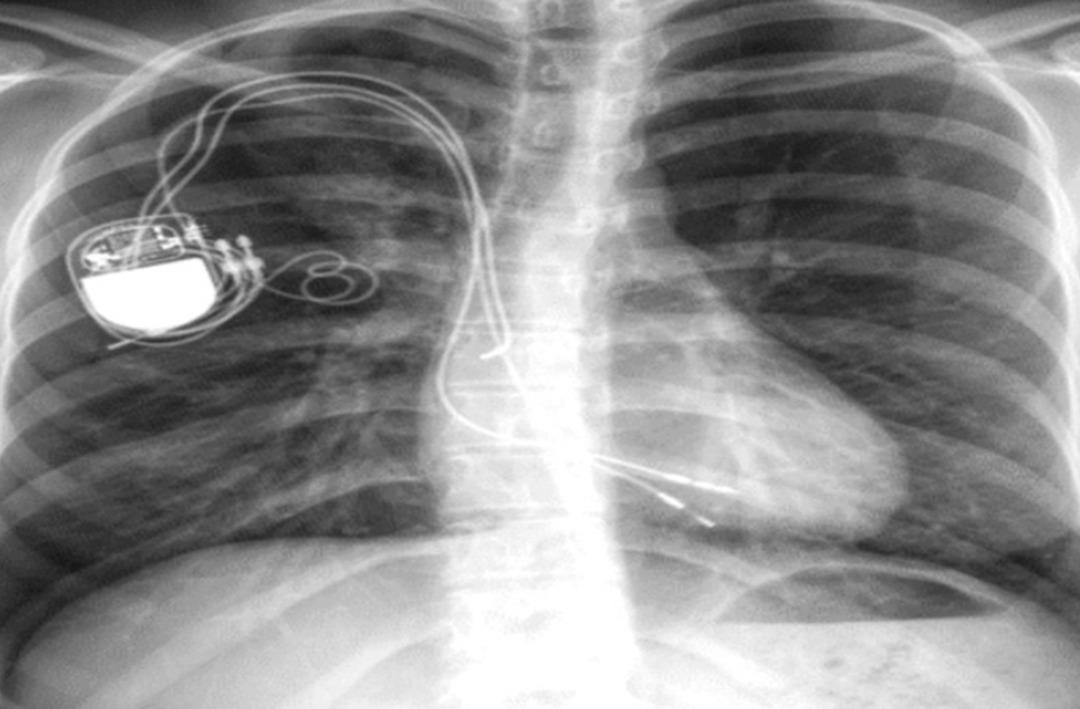

Çalışkan'ın tomografisine baktığında 20 yıl önce takılan kalp pili kablosunun artık hastanın organlarıyla birleştiğini, kablonun birçok damarın içine girip çıktığını, çıkartılırsa hastanın hayatını kaybedeceğini anlayan Kuyumcu, kabloyu çıkarmadan tedavi etme üzerinde yoğunlaştı.

Hastaya takılacak yeni pil sisteminin verimli çalışması için daha önceden uygulama örneği olmayan eski pilin kablosunun dış katmanına zarar vermeden içindeki metal iletken kabloları tek tek çıkarma yöntemi fikrini bulan Kuyumcu, hastanın da onayını aldıktan sonra ameliyatı uygulama aşamasına geçti.

Kuyumcu, kendisine operasyonda yardımcı olan Kardiyolog Doç. Dr. Bayram Ali Uysal'la yaklaşık 3 saatte açık kalp ameliyatı yapmadan hastanın karın boşluğundan ulaştıkları kabloyu keserek dış katmanına zarar vermeden içindeki 20'şer santimetrelik onlarca metal kabloyu çıkardı. Bu müdahalenin ardından yeni kalp pili sistemi (jeneratör ve lead) takılan Çalışkan, ertesi gün hastaneden taburcu edildi.